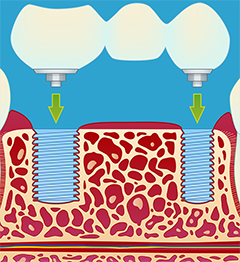

3.) Fremstilling og montering av kronen (fig III-V). Det er en tanntekniker som lager selve broen. Broen blir vanligvis festet med små skruer, slik at den senere kan tas av ved behov. Dette krever vanligvis 2 eller flere tannlegebesøk.